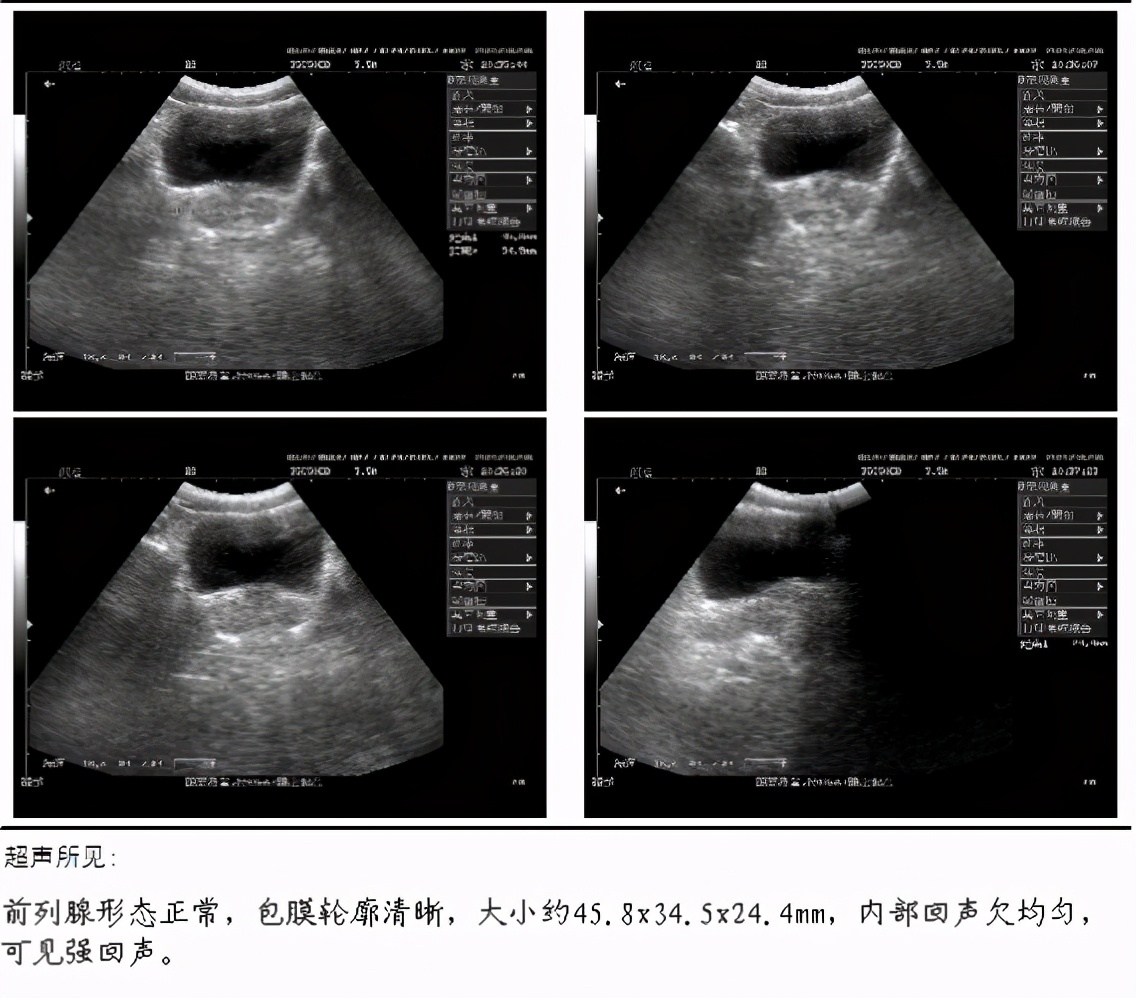

前列腺B超:

前列腺形态正常包膜轮廓清晰,大小约45.8x34.5x24.4mm,内部回声欠均匀,可见强回声。

确诊为慢性前列腺炎伴钙化